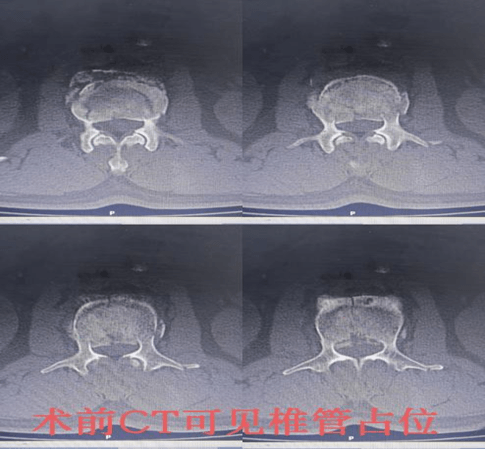

患者李某某,男,59岁,系“摔伤致腰背部疼痛伴活动受限2小时余”入院;入院后予以完善相关检查,CT示:腰2椎体爆裂性骨折,侵占部分椎管,L2左侧横突骨折。MRI提示:L2椎体压缩性骨折,L2右侧椎板骨折;腰椎退行性变;L2/3、L5/S1椎间盘突出。摄片提示:L2椎体楔形改变,椎体前缘压缩1/3。

骨伤一科陈孝贵主任指出:根据患者病史、体征及影像学表现,患者腰椎压缩性骨折(L2 爆裂性)诊断明确,对于脊柱骨折保守治疗患者,需要长期卧床,极易出现褥疮、坠积性肺炎、下肢静脉血栓形成、肺栓赛等并发症,保守治疗椎高丢失会引起腰椎后凸畸形、慢性腰疼及继发腰椎不稳等后遗症,对于该患者,手术指针明确,手术目的:恢复椎高及清理椎管占位,促进早期下地,减少并发症及远期后遗症。建议患者行微创手术治疗方案-经皮椎弓根螺钉复位内固定术,患者及其家属同意并积极配合治疗方案,积极术前准备,在排除手术禁忌后,陈主任为其行手术治疗,手术顺利,术后2天即可佩戴支具下床活动。